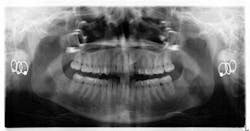

When a full permanent dentition is present (with the exception of impacted canines), the labial/palatal position of the canine will have an influence on what the provider can do. (1) Arguably, obtaining a CBCT is considered mandatory and will allow for a more inclusive treatment plan creation. If angulation is favorable, then consideration to remove the primary canine and wait six months to see if there is movement of the permanent canine is an option. If extraction of the canine(s) is needed, then a premolar substitution, which is dependent on occlusion, can be used in the space. An implant can also be an appropriate alternative. When pulling a canine into the occlusal arch, there is risk involved. Trauma to adjacent teeth (root resorption) and ankylosis are some of the most common complications.The patient was put in full orthodontics and referred to a surgeon for extraction of the primary canines, exposure, and placement of retention on the impacted canines to pull them directly down from their current position.

A ballista appliance was used to prevent a facial pull of the canines in order to avoid and prevent resorption of the roots of the lateral incisors. As movement progressed over the course of the next year, eruption of the canines was considered a success. Once in position, they will be pulled facially into occlusion.